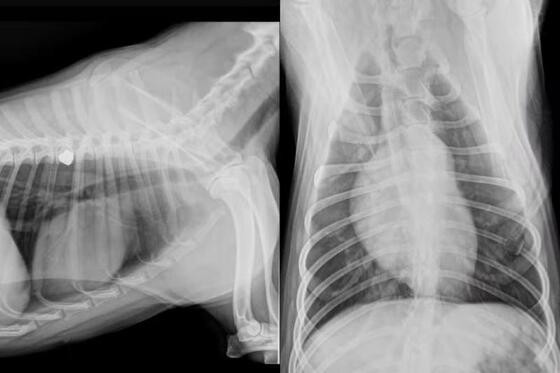

A clínica veterinária responsável pelo atendimento confirmou que, apesar de não correr risco de morte, a cachorra perdeu a visão do olho atingido. Um exame de raio-x revelou que o projétil ficou alojado próximo à costela do animal, exigindo acompanhamento contínuo.